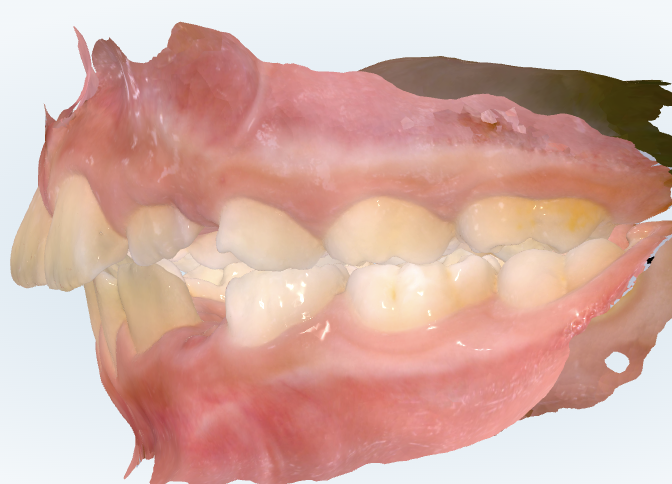

初診時の画像診断

左上の前から3番目の歯(犬歯)が生えるスペースがありません。

奥歯が出っ歯の噛み合わせをしています。

上の前歯の真ん中のラインが左にずれています。

上の奥歯が本来の位置より歯1本分くらい前にある“出っ歯傾向”があります。

前歯が少し内側に並ぶことで、見た目としての出っ歯は軽度です。